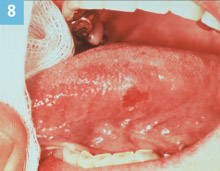

Figure 8. Squamous cell carcinoma. |

History of the lesion is not always helpful in the early stages of a lesion or condition. This lesion is indeed a classic! An erythroplakic lesion is observed in the dental office on a recare visit. It is on the left lateral boarder of the tongue, at the junction of the anterior and middle thirds, measuring 5 mm x 7 mm. (Figure 8). The patient has not noticed it and it is asymptomatic. The dental hygienist asks the patient questions related to the lesion. The dentist cannot establish a cause, eg, if the patient had a rough surface on a fractured tooth that could have caused this lesion or if the patient bit his tongue. This lesion was diagnosed as squamous cell carcinoma upon microscopic evaluation. However, the patient would have never seen the oral surgeon for the biopsy if the dentist said, “Let’s watch it until next recare.” These subtle lesions are the challenges. So again, when in doubt, refer it out!